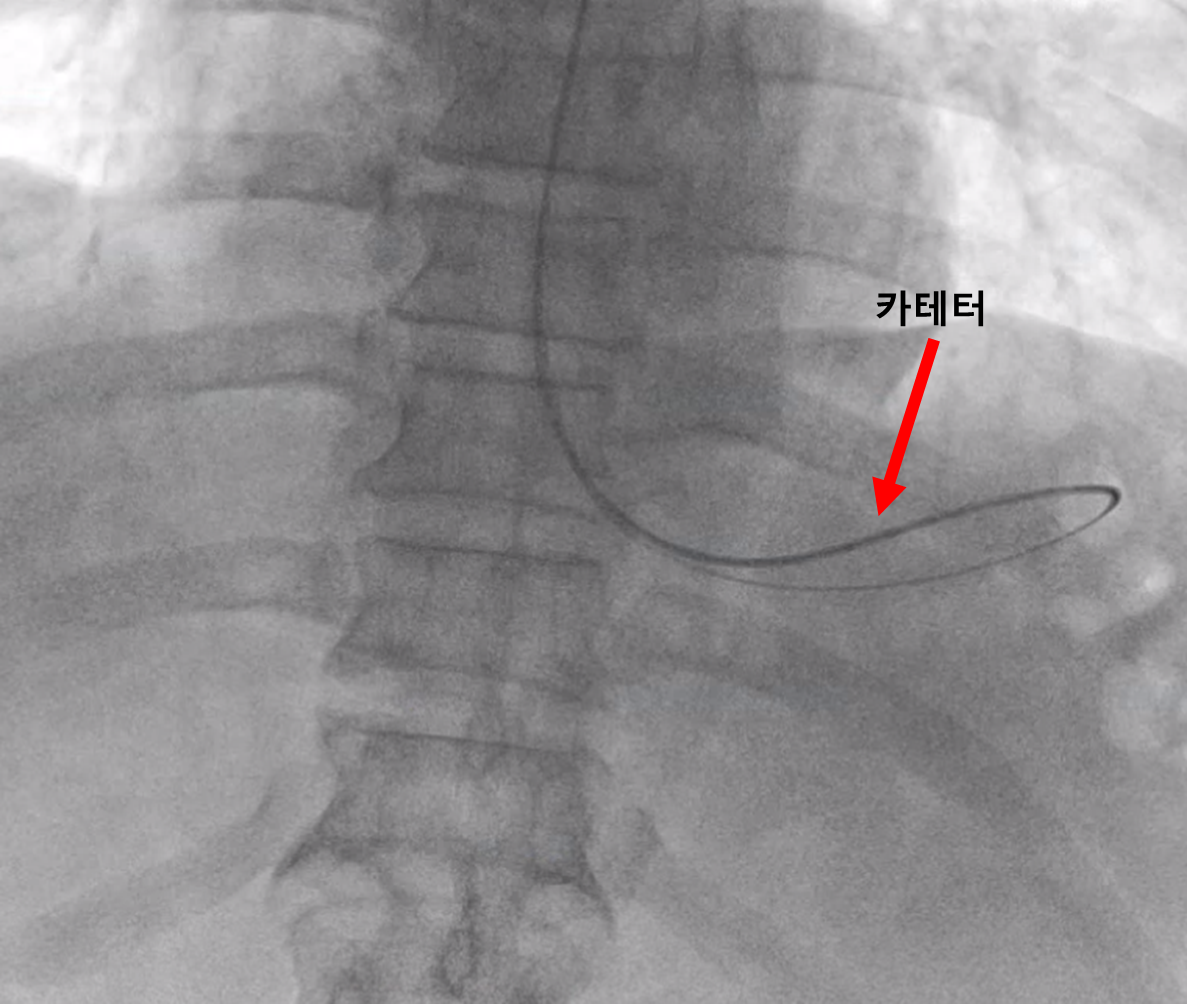

바늘이 위 속으로 잘 들어간 것을 확인한 다음 와이어를 넣습니다.

와이어가 잘 들어갔다면 위 모양 대로 와이어가 말리는 모습을 확인할 수 있고요.